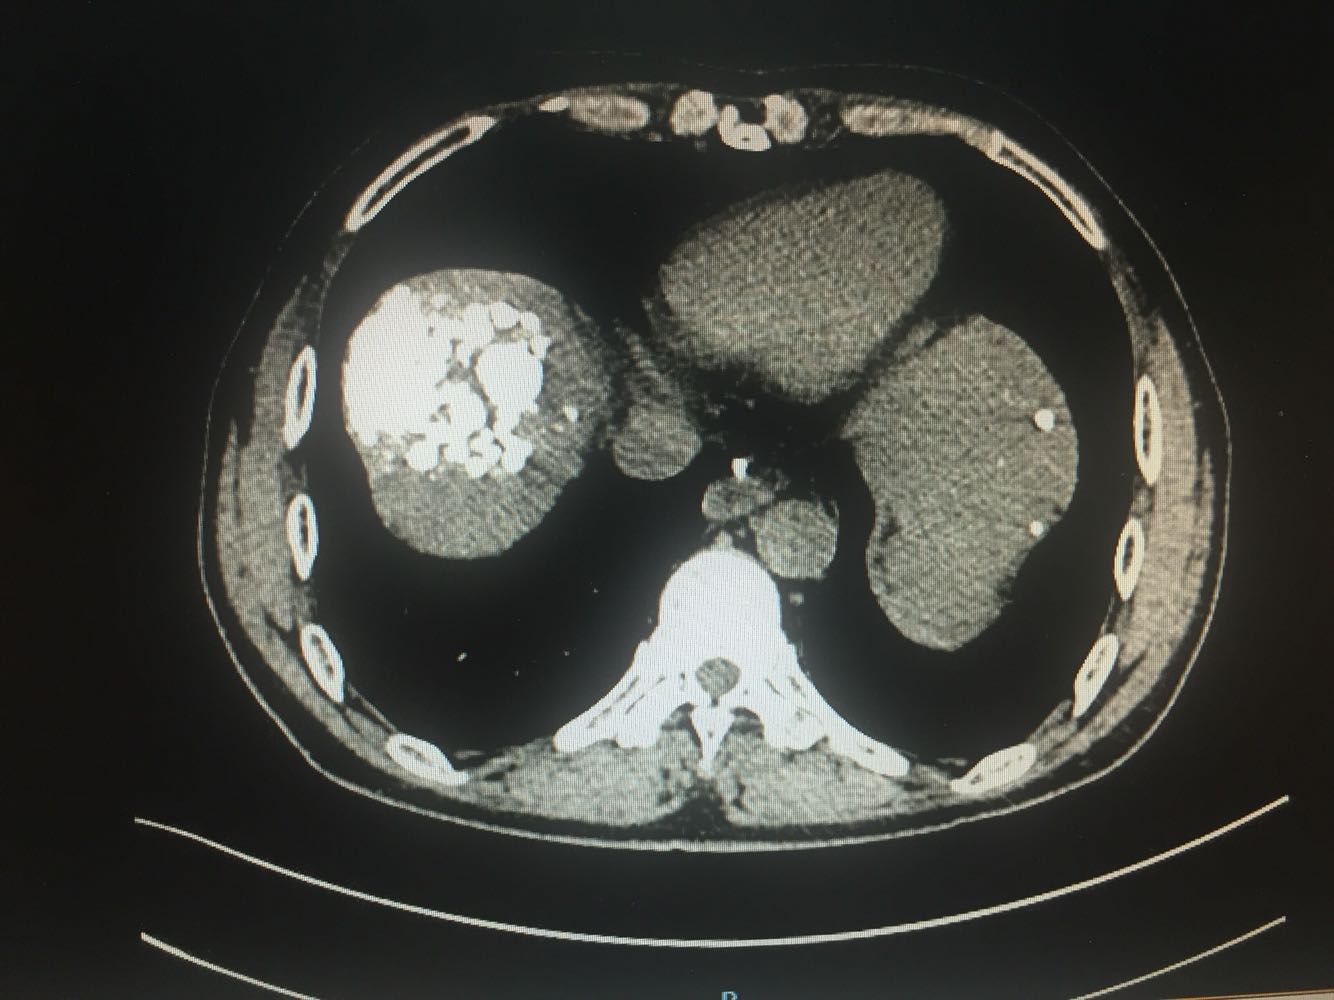

出院一月后复查,行增强CT扫描,肿瘤明显缩小,肝功能正常,乙肝病毒复制转阴,建议继续口服恩替卡韦抗病毒治疗